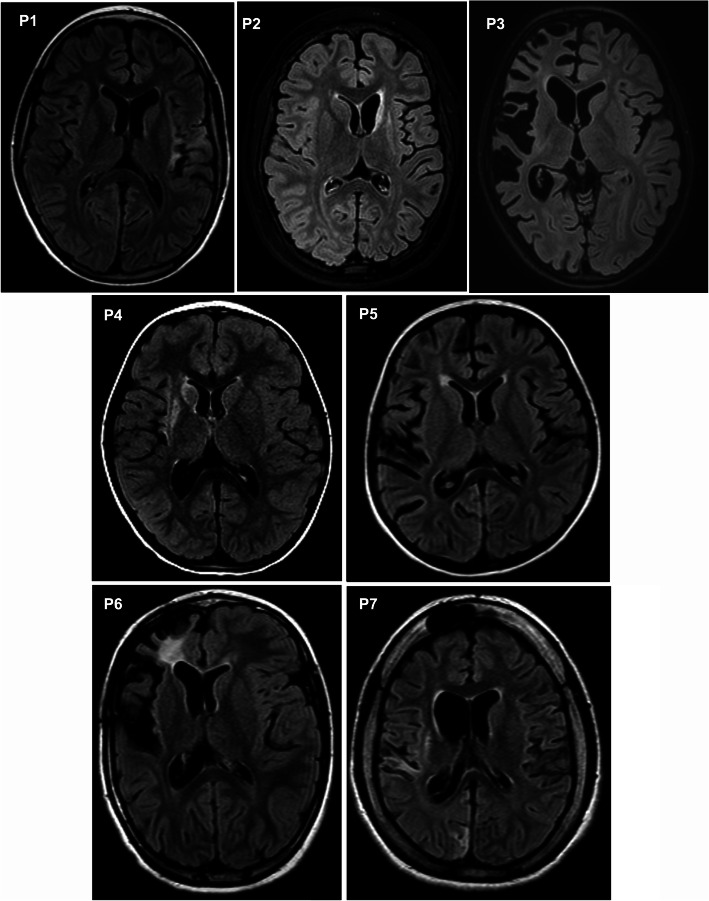

Fig. 2.

Magnetic resonance imaging (MRI) at the time of surgery. Axial fluid-attenuated inversion recovery (FLAIR) MRI sequences of the brain showing differently pronounced atrophy of the affected hemisphere in every patient at the time of surgery are displayed. In addition, various inflammatory and glial changes in the affected hemisphere can be observed in every patient

All patients were children with normal psychomotor development until RE onset; in all of them, RE began with a focal epileptic seizure of variable semiology (median age 4 years, range 2–9; 71% females). After a variable period (median 1 month, range 0.5–5), all children developed intractable epilepsy followed by individual motor and cognitive decline. The correct diagnosis was made after a delay from first disease symptom onset (median 9 months; range 1–115). Immunotherapy was introduced at the time of intractable epilepsy in all cases; the exception was P4, who received a low dose of oral steroid in a prodromal phase due to an abnormal brain imaging. In addition, P2 and P6 received immunotherapy prior the correct diagnosis because they had other clinical symptoms (cerebellar syndrome in P6) and abnormal brain imaging (P2) suspected from brain inflammation. The first choice for all was intravenous methylprednisolone (IVMP) with an oral taper and/or IVIG. Subsequent T cell-targeted immunotherapy was introduced in P1–6 (i.e., AZA, TAC or intravenous CPA). Therapy was escalated further in the two patients with the dominant hemisphere affected. P1 received one cycle of RTX after 9 months of unsatisfactory therapy with TAC and then one cycle of ALEM that was combined with intrathecal methotrexate (ITMTX) in irregular intervals and long-term mycophenolate mofetil treatment (MMF) [13]. P2 was escalated to NAT after four doses of intravenous CPA. None of the therapies reversed the refractory epilepsy, although all patients received some temporary positive impact on their clinical state. In P1 alone, therapeutic management stopped the motor (not cognitive) decline and modified the course of intractable epilepsy (periods of relative seizure stabilization alternated clusters of seizures) [13]. Hemispherotomy was finally performed in all of the children (median 26 months after disease onset, range 12–126). An initial disconnection was incomplete in four patients; they thus were re-operated (P2, P4, P5 and P7). All but one patient (P7: the one with the longest disease duration and minimal immunotherapy) remained seizures free after a complete disconnection of the affected hemisphere. The clinical data are summarized in Fig. 1 and Additional file 1. The individual atrophy of the affected hemisphere at the time of neurosurgery is captured in Fig. 2.